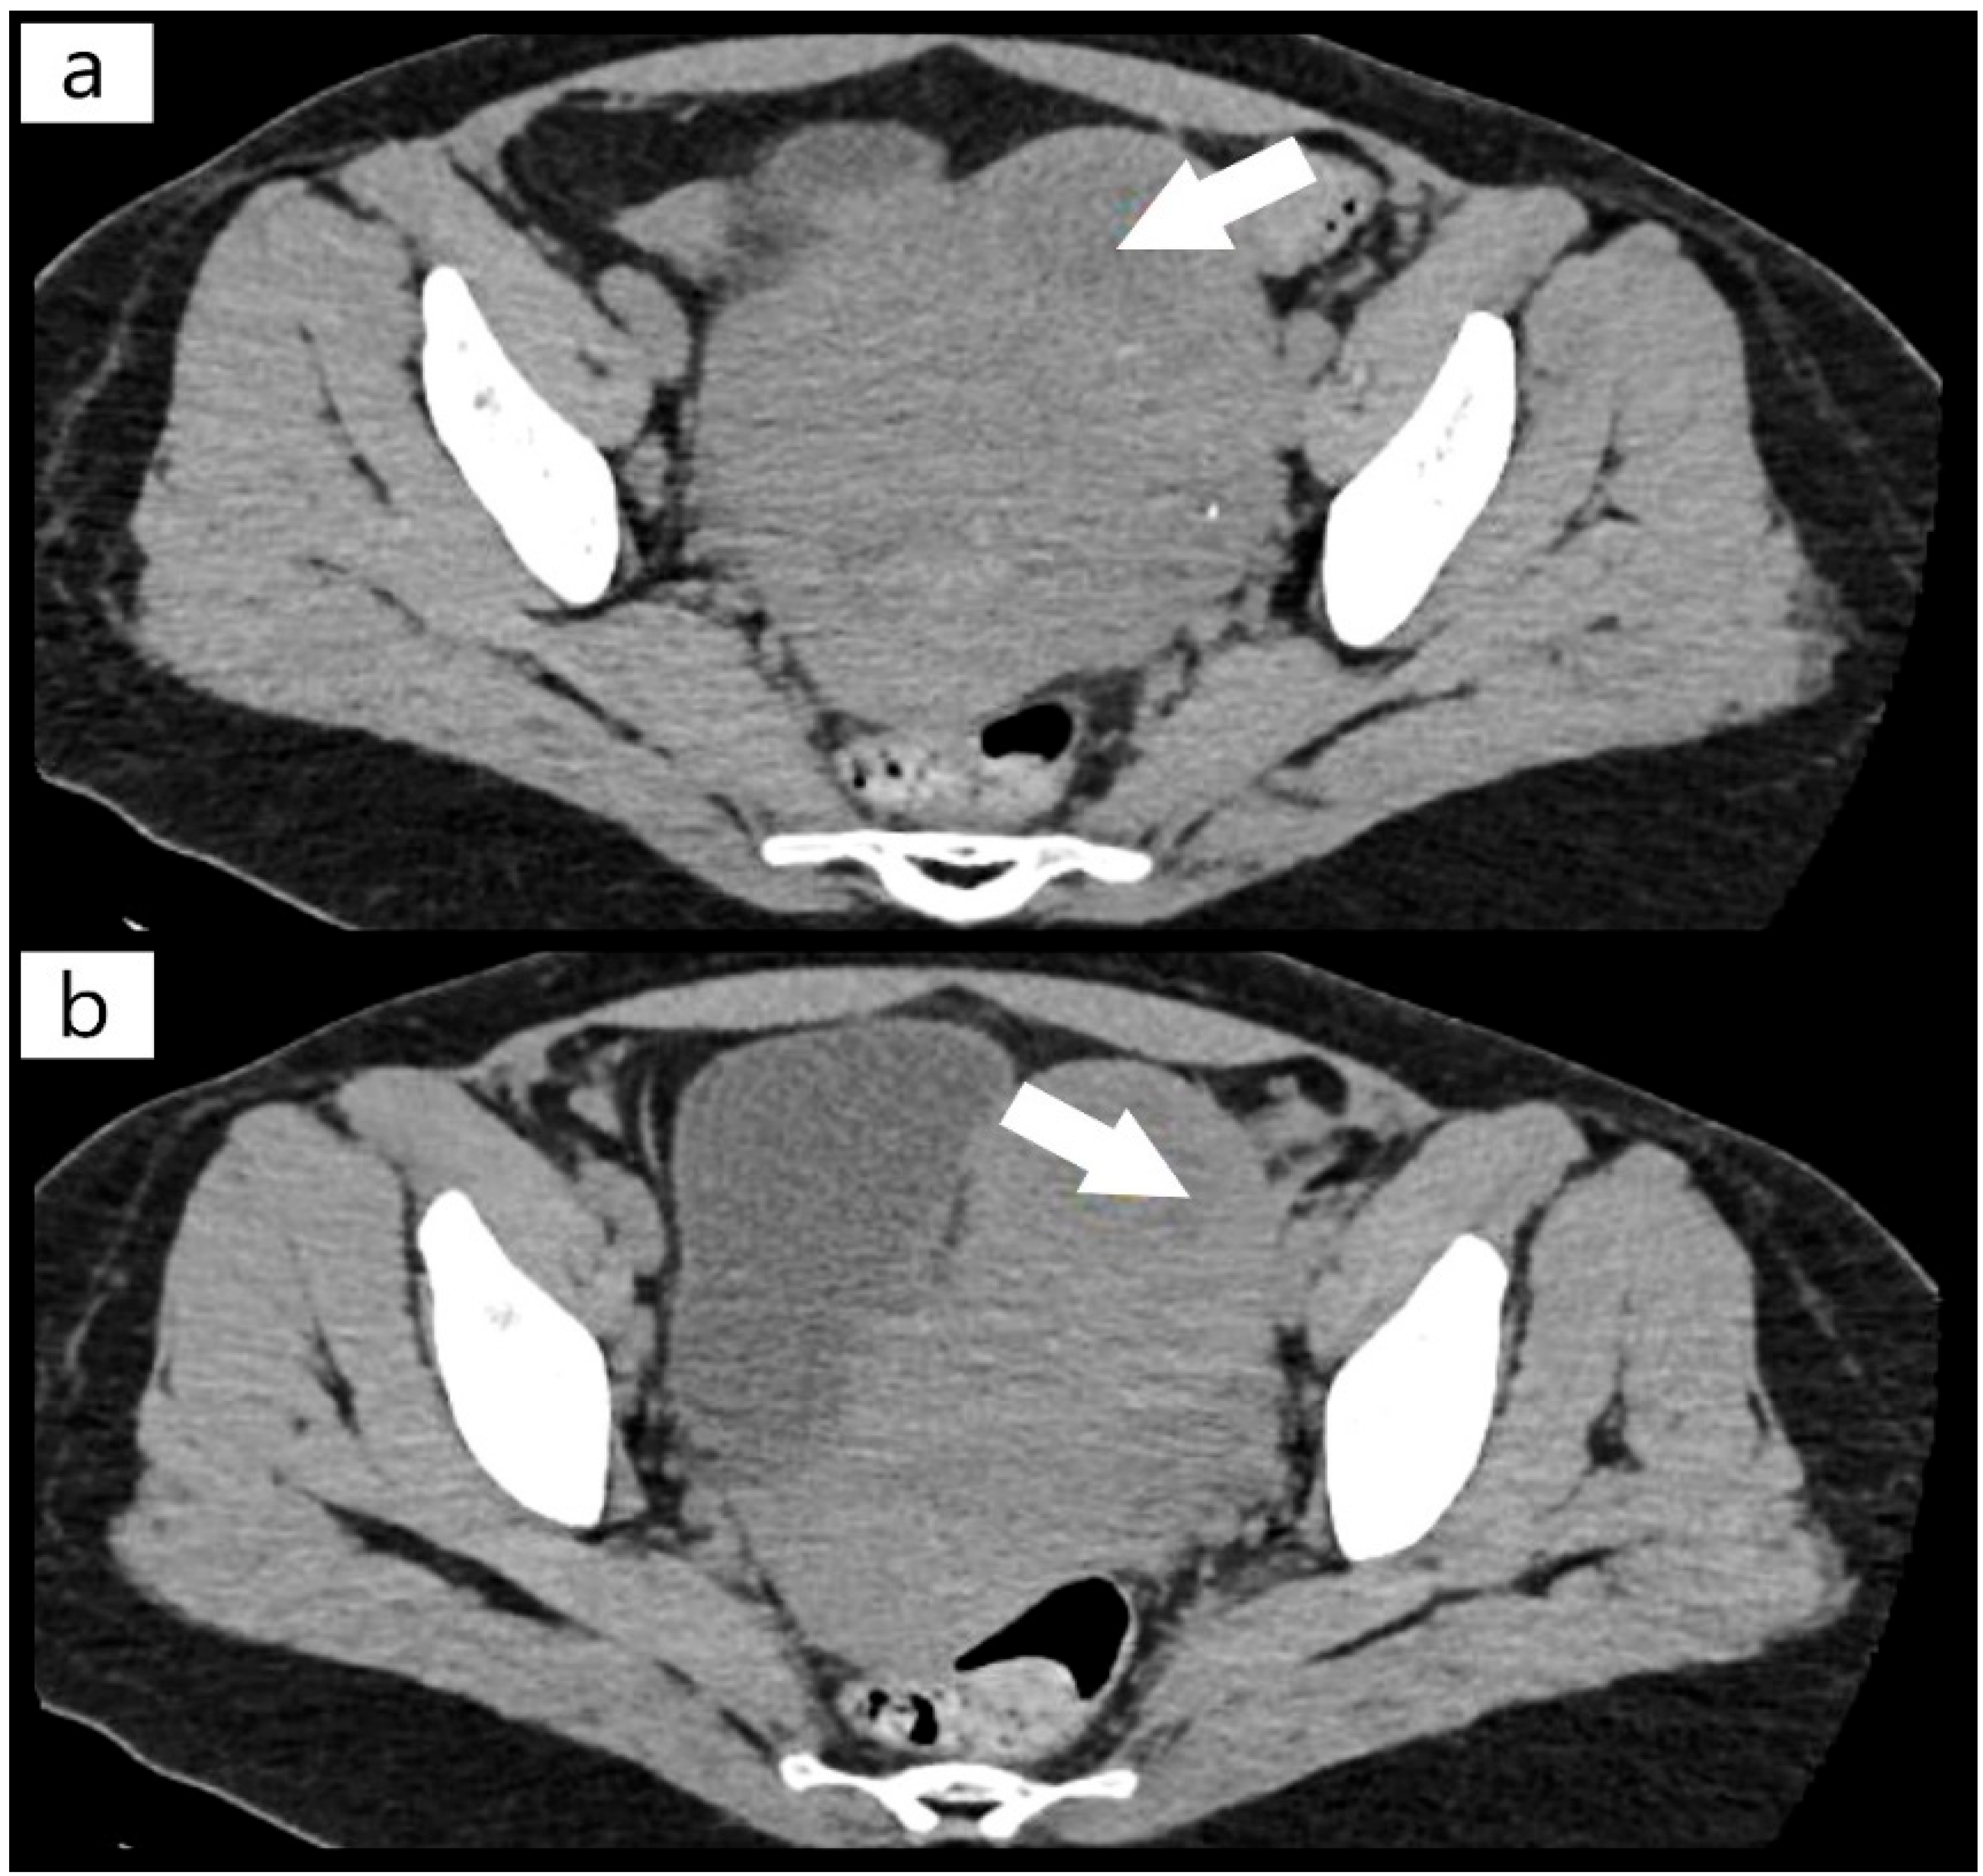

2. Case Report